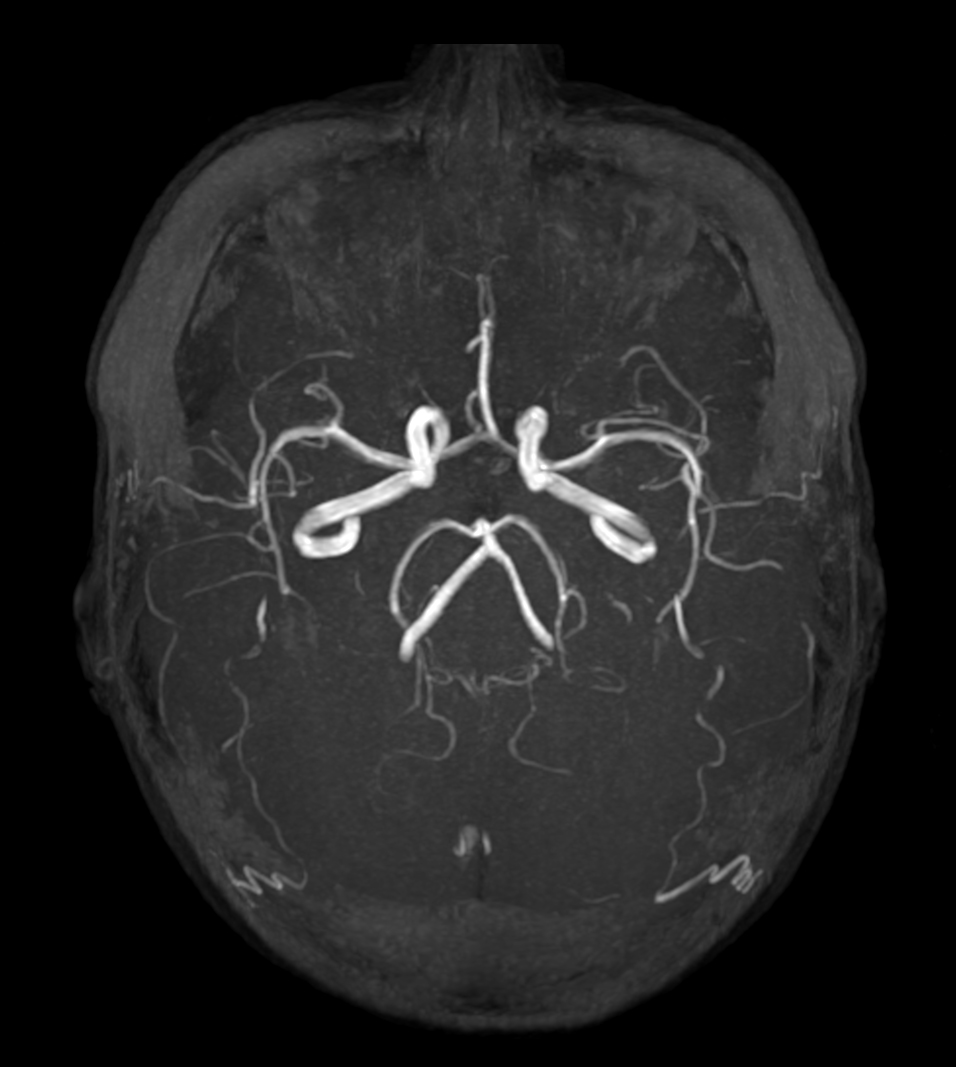

Axial 3D Inflow

Coronal 3D Inflow

Sagittal 3D Inflow